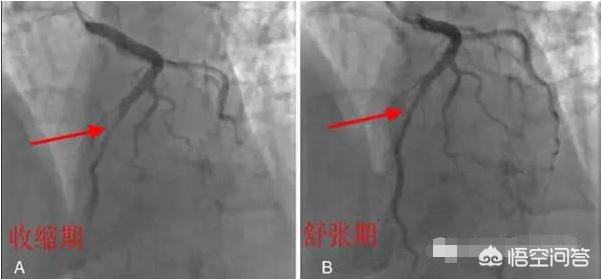

b. 心筋ブリッジ

このタイプはもっと不運だ。通常であれば冠動脈は心外膜の下の心筋の表面にあるが、「心筋ブリッジ」に罹患している人の場合、冠動脈が心筋の下に埋もれている部分があり、冠動脈の上を覆っている心筋を「心筋ブリッジ」と呼ぶ。冠動脈上の心筋橋の圧迫の程度によって、一般に安静時の心電図上では圧迫が軽度で無症状であるのに対し、40%以上の圧迫があると胸部圧迫感や胸痛、狭心症などの臨床症状が現れるとされている。下の図は、1心周期の間に心筋ブリッジによって冠動脈が圧迫される様子を示したもので、圧迫されると血管の全区間が細くなる。

それだけでなく、圧迫された冠動脈は、繰り返し圧力とねじれを受けるため、冠動脈攣縮を起こしやすくなる。また、血管の近位部では血液の乱れ(血液が血管内を十分にスムーズに流れない)などの血流障害があるため、冠動脈の動脈硬化(閉塞)が起こりやすくなり、その上、プラークの破裂、出血、血栓症、けいれんなどが起こり、急性冠症候群の発症につながる。この状況は本当に不運で、提案としてはやはり昔から言われているように、運動量、定期的な見直しである。今のところ、特に良い方法を聞いたことがないからだ。しかし、より多くの人がこの先天性異常を理解すれば、この状況は避けられる。